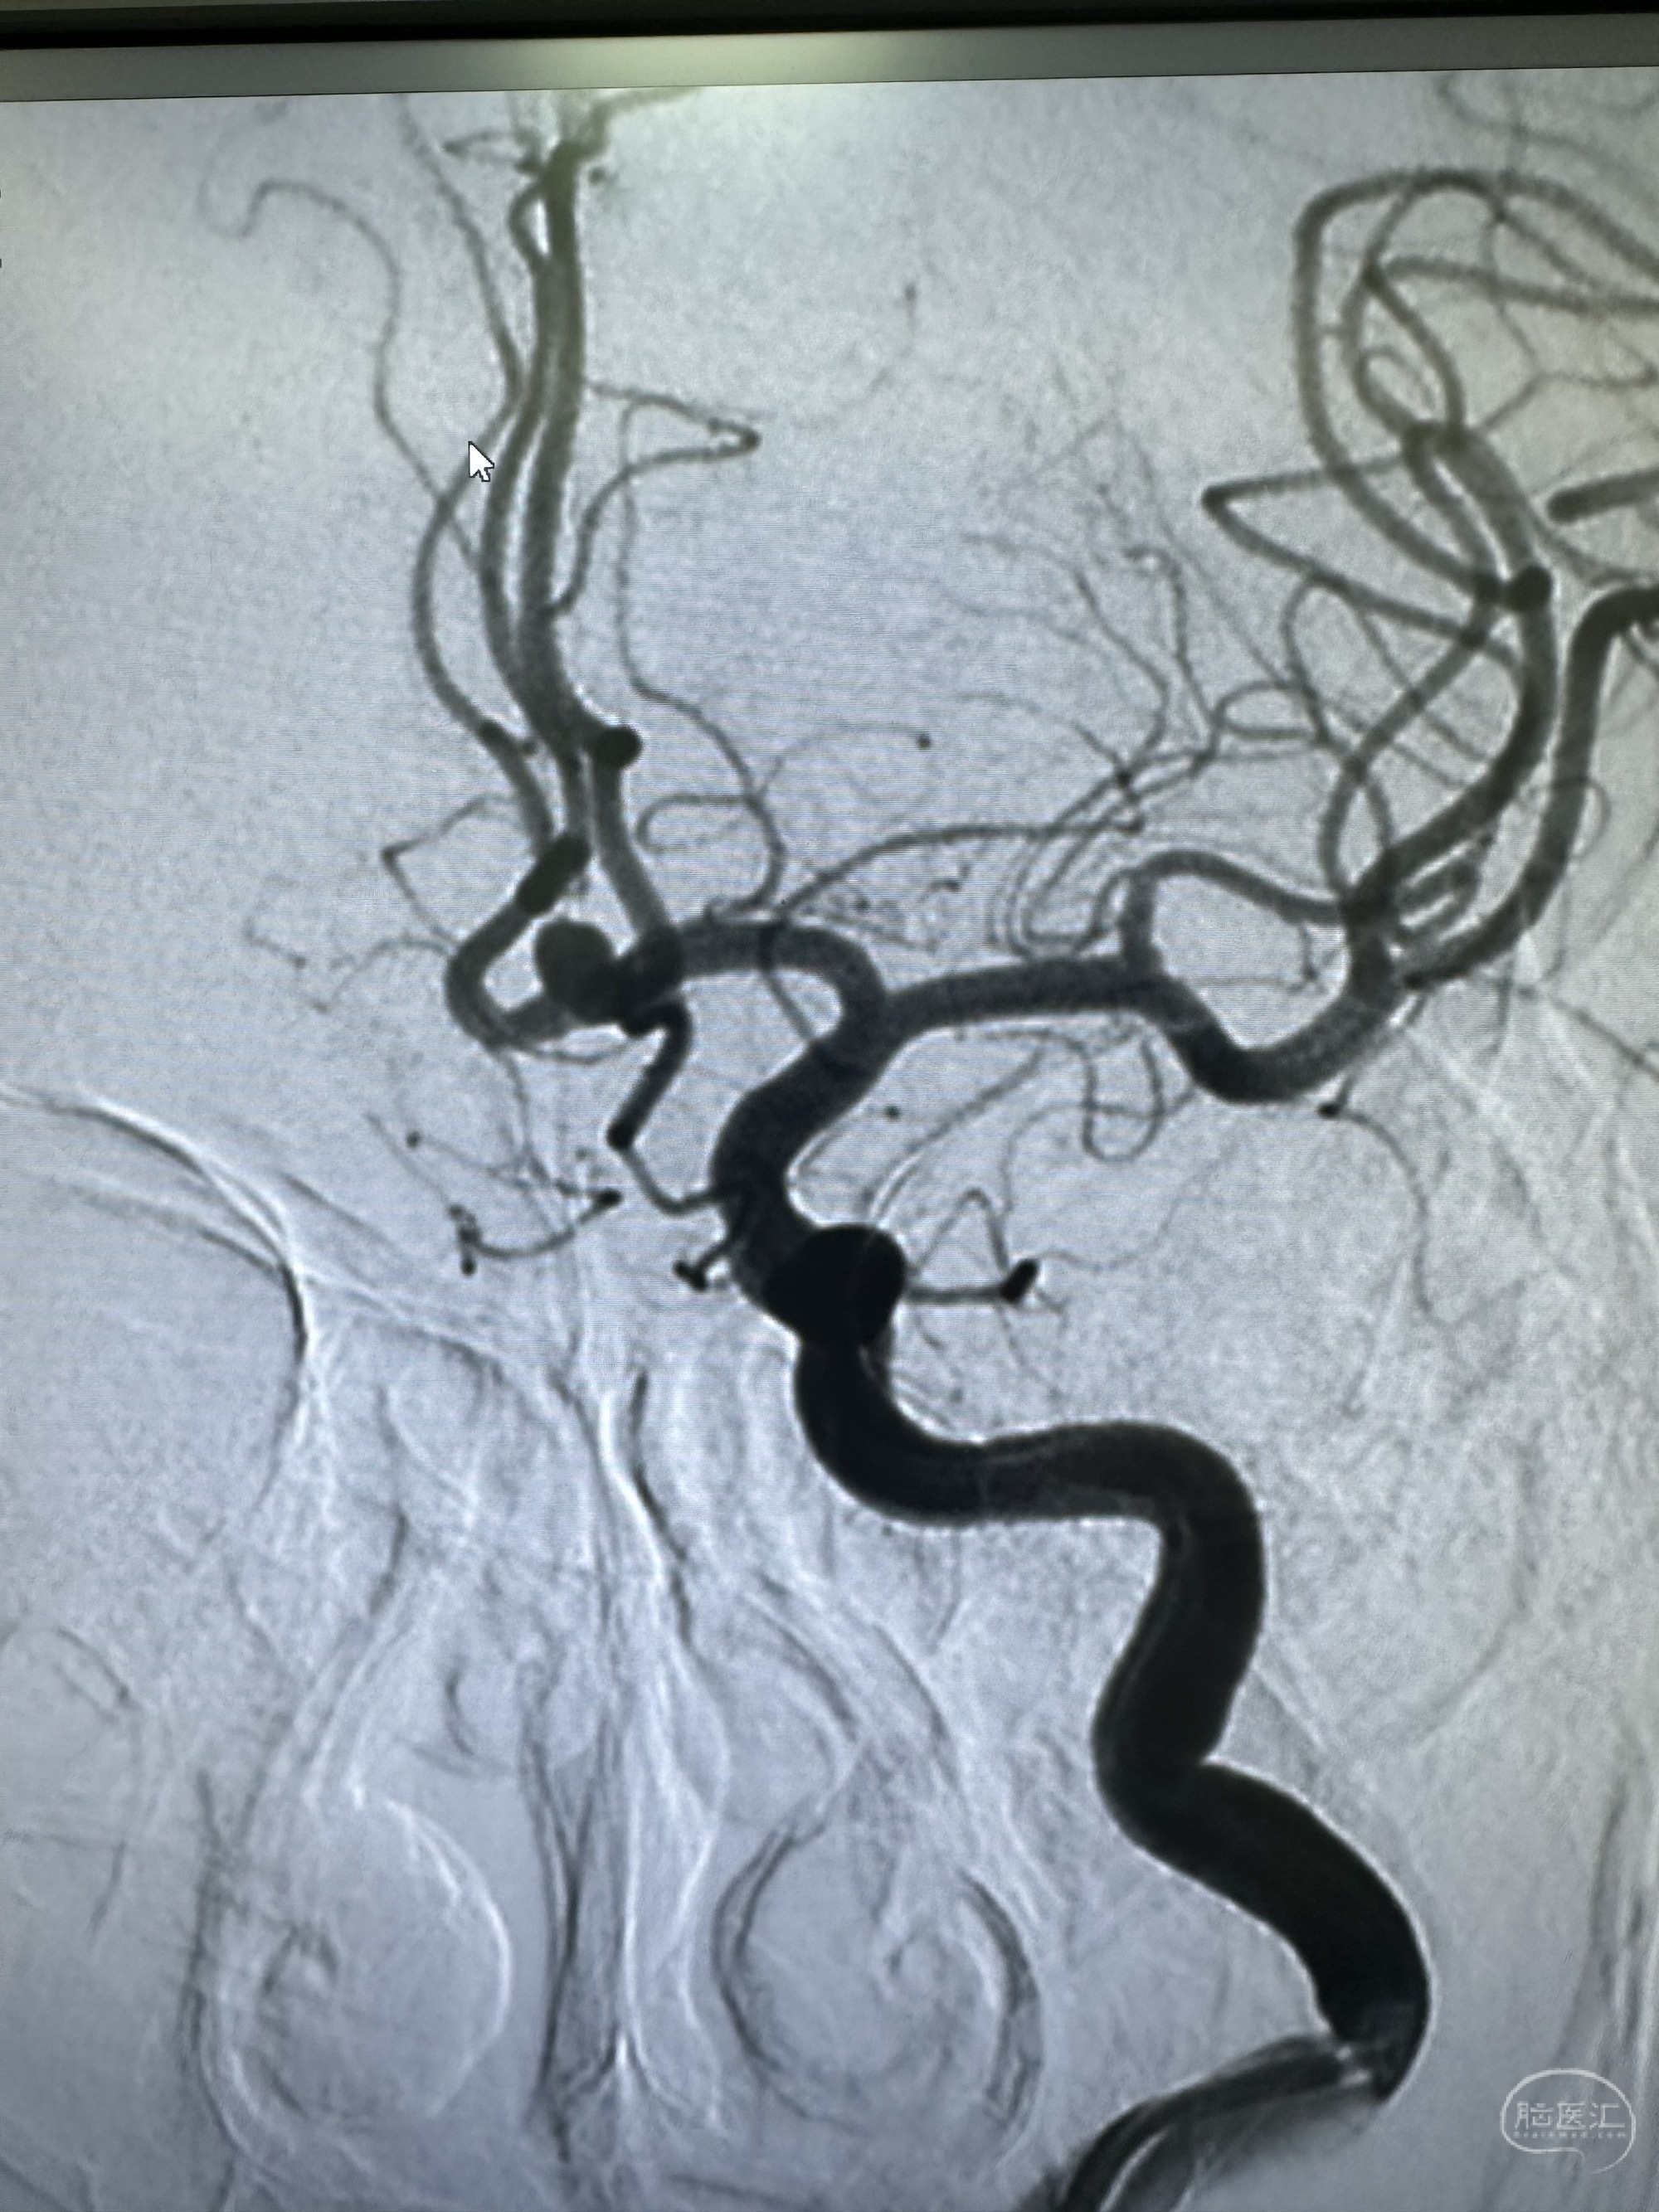

左侧造影